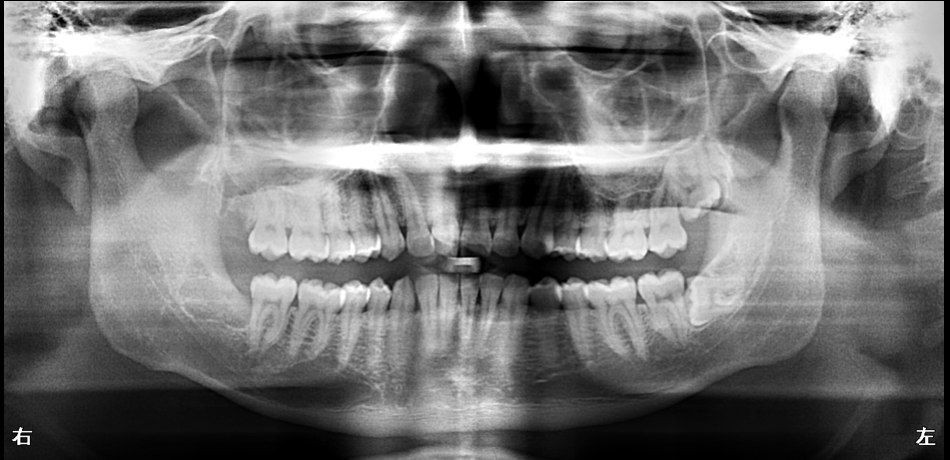

【60代男性】

歯がボロボロで見た目が気になる

【精密根管治療・歯周再生療法・セラミックによる包括治療】

- 担当医

- 生野 誠

- 主訴

- 奥歯がグラグラして噛めない

笑うことに強いコンプレックスがある

- 期間

- 約2年間(精密治療と段階的な全顎修復を行いました)

- 費用

- 300万円

- 治療内容

- 精密根管治療:マイクロスコープを使用し、感染部位を徹底的に除去。

歯周組織再生療法:グラつきのある歯をできる限り保存。

咬合治療:開咬を考慮し、噛み合わせを安定させる設計。

セラミック修復:自然で美しい見た目に改善し、全顎的な審美性を回復。

- 治療に伴うリスク

- 治療期間が長期にわたる場合がある。

状態によってはすべての歯を保存できない場合がある。

自費診療のため保険診療に比べ費用負担が大きい。